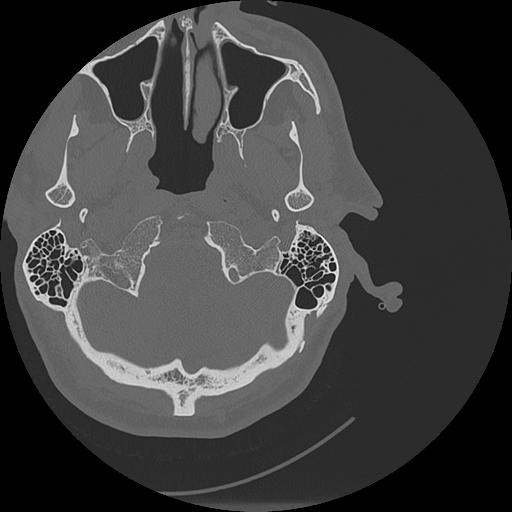

7 HUESO,,Vol,0.5,HUESO,,